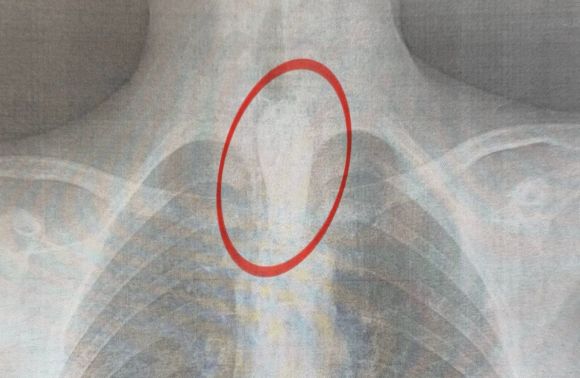

Під час вечері він з'їв великий шматок шашлика, який застряг у стравоході.

У дитини розпочалося порушення ковтання, активна слинотеча, вона не могла навіть ковтати власну слину, відчувала значний дискомфорт, страх і утруднене дихання.

"Стравохід має природні звуження: на рівні шиї, біля аорти та на вході до шлунка. У цьому випадку шматок м'яса зупинився на другому звуженні. Слина постійно виробляється, але не може пройти далі, що викликає сильну слинотечу, відчуття стороннього тіла за грудиною і страх. Дитина не могла нормально дихати", – розповів торакальний хірург нашого Центру Олександр Колодій (Олександр Колодій).

Операцію провели вночі – о 2:00 хлопця терміново доправили до операційної, де команда фахівців виконала ригідну езофагоскопію. Втручання тривало близько години: великий шматок м’яса видаляли поетапно, щоб не пошкодити стінки стравоходу.

"Це дуже делікатна хірургічна робота. Необхідно діяти обережно, щоб не спричинити перфорацію стравоходу", – пояснює торакальний хірург Олександр Колодій.